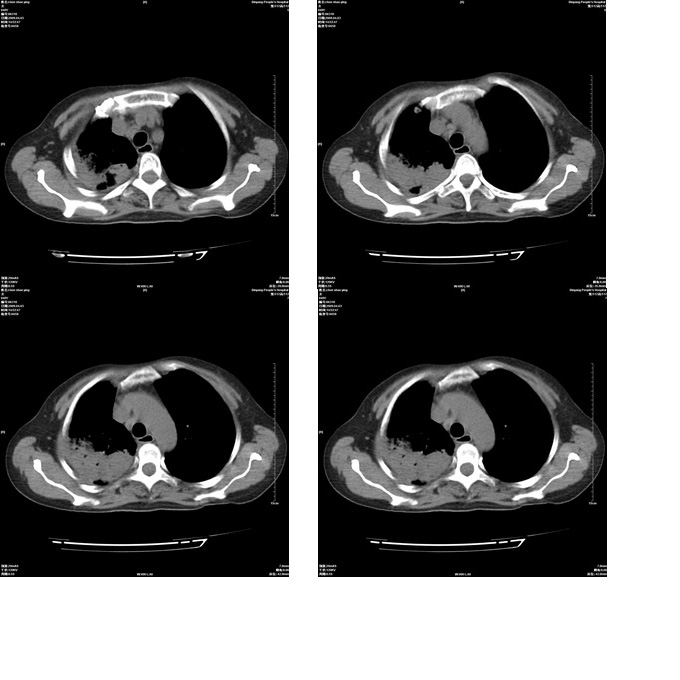

患者,女,48岁,发热伴陈发性咳嗽5天,偶尔痰中带血。体温约38°~40°;白细胞明显减低0.85x10的9次方/升。入院后抗炎、抗痨一周复查病灶明显进展。

白细胞这么低病因方面我觉得不是很好的感染。

建议痰培养检菌+药敏试验.血项的进一步的检查或检骨髓.

肺部感染,患者白细胞那么低,什么病菌都有可能的,不知有何原发病,服用搞免疫制剂?爱滋/

患者已做骨穿,节后做气管镜;有结果会上传。谢谢参与讨论。